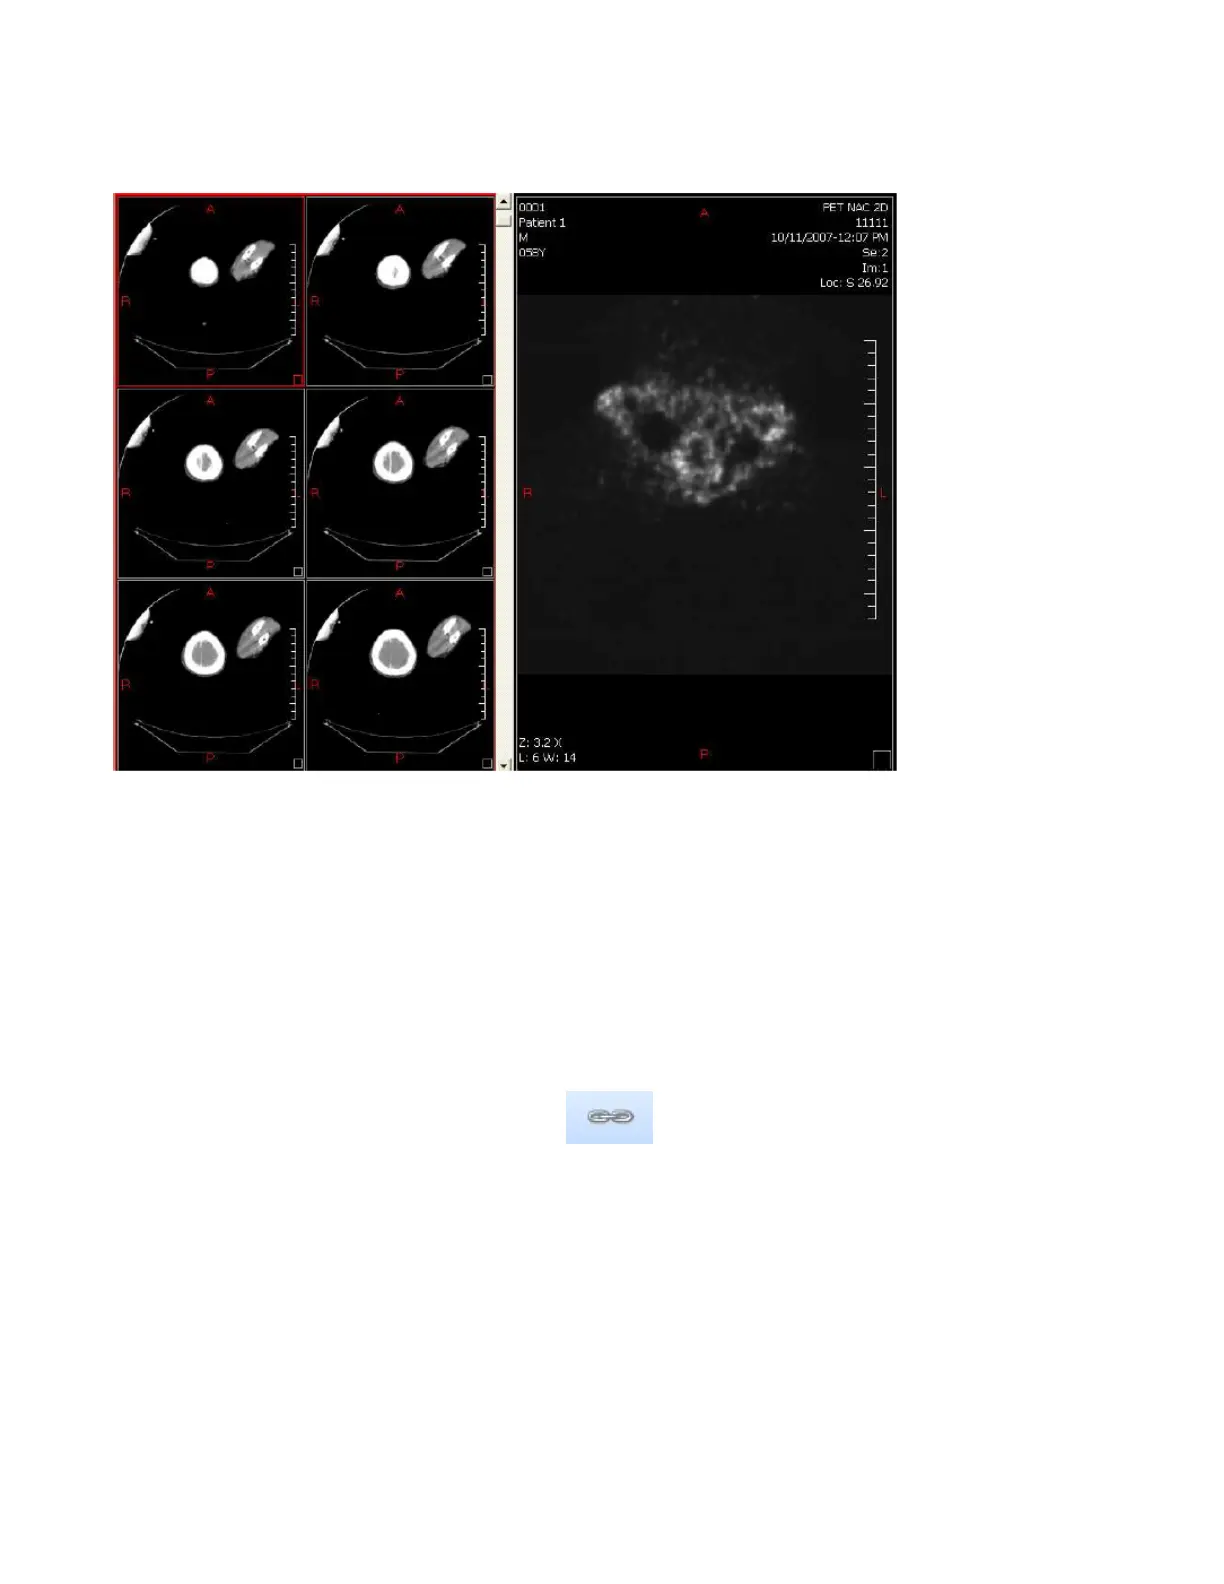

1.4.2 Images Layout

The Images Layout tool allows you to visualize multiple Images from the same Series at the

same time.

Simply click on the Images button and select a Layout.

1.5.1 Comparative Mode

The Comparative Mode allows you to scroll into different Series at the same time.

Select a 2x1 Series Layout, add a Series in each Viewport, Click on comparative Mode and

scroll on a Series. Both Series will scroll at the same time.